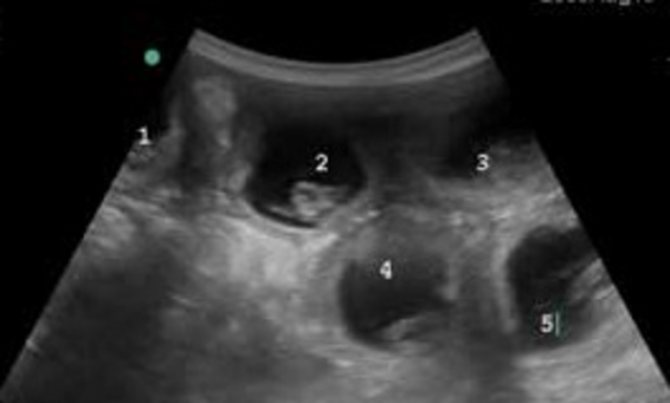

Помимо взятия анализов, ветеринар проводит внешний осмотр и пальпацию животного. Для обнаружения плодов делают УЗИ, а для определения их точного количества и положения – рентген. Рентгеновский снимок признается самым точным методом диагностики, но проводится не раньше 50 дня после вязки.